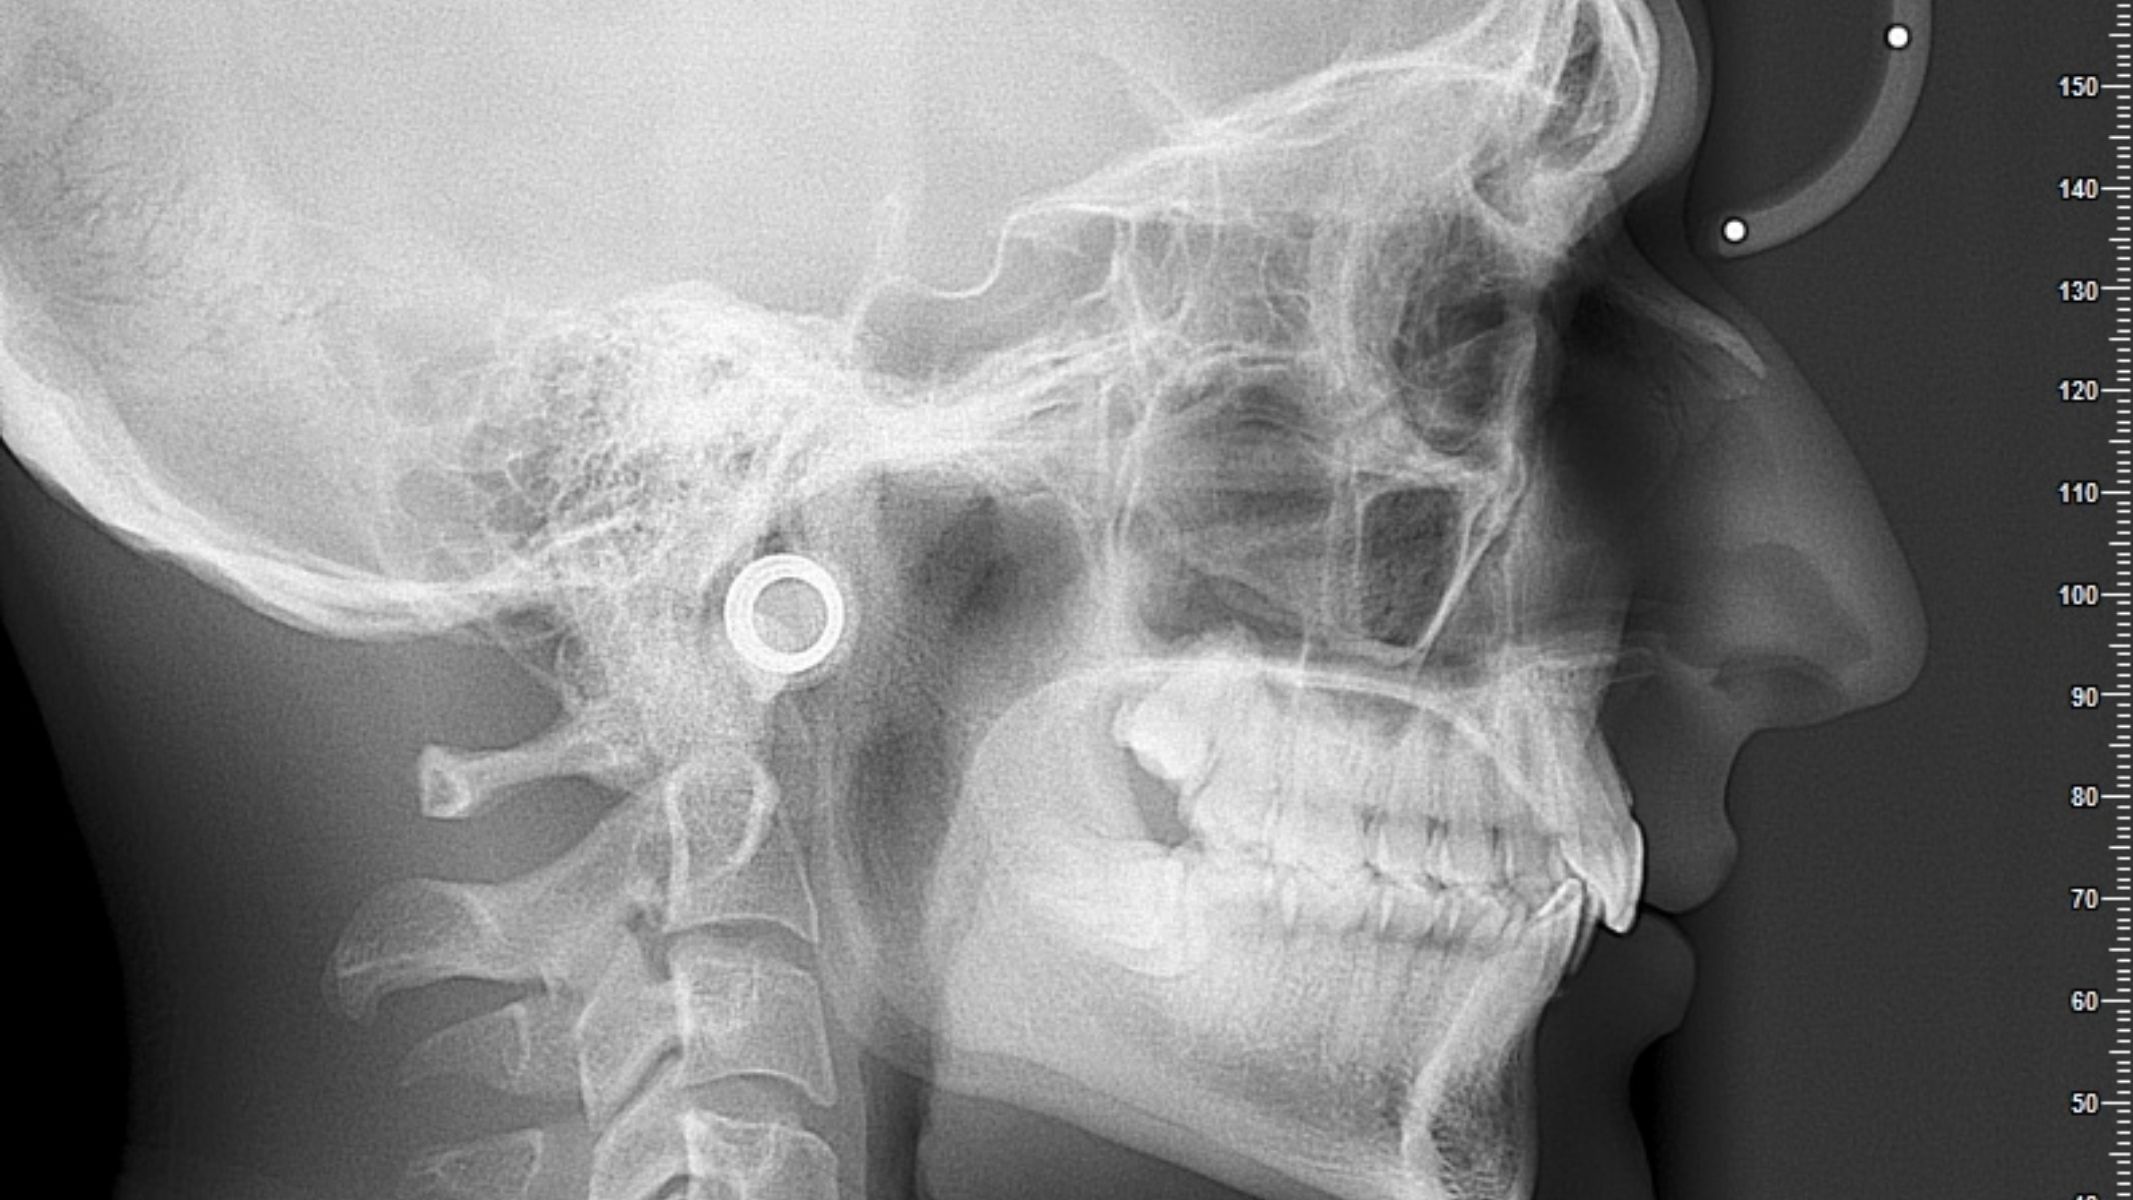

X-quang hàm mặt

X-quang là phương pháp đầu tiên được sử dụng khi bệnh nhân có triệu chứng bất thường tại vùng hàm. Tuy khả năng mô tả chi tiết không cao, X-quang vẫn giúp phát hiện:

- Hình ảnh tiêu xương hoặc mảng xương bị phá hủy.

- Vùng cản quang bất thường.

- Ranh giới tổn thương bất đối xứng.

X-quang thường được chỉ định khi bệnh nhân xuất hiện đau hàm, lung lay răng hoặc biến dạng xương. Đây là bước khởi đầu giúp phát hiện dấu hiệu nghi ngờ ung thư.

Đặc điểm hình ảnh học

Trên các phương tiện chẩn đoán hình ảnh như X-quang, CT, MRI hoặc PET-CT, ung thư xương quai hàm có thể biểu hiện bằng nhiều dạng khác nhau tùy vào loại mô bệnh học (ví dụ: Osteosarcoma, chondrosarcoma, Ewing sarcoma). Các đặc điểm hình ảnh thường gặp bao gồm:

- Tiêu xương dạng loang lổ hoặc lan rộng, ranh giới không rõ ràng.

- Hình ảnh phá hủy xương không đối xứng, thường không tuân theo cấu trúc giải phẫu bình thường.

- Đường viền xương bị bào mòn, mờ hoặc gãy đoạn.

- Xâm lấn mô mềm kế cận, quan sát rõ hơn trên MRI.

- Di căn hạch cổ (nếu có), phát hiện trên CT hoặc PET-CT, tuy không phổ biến với sarcoma, nhưng cần theo dõi.

Việc chẩn đoán hình ảnh đóng vai trò định hướng, tuy nhiên sinh thiết mô bệnh học vẫn là tiêu chuẩn vàng để xác định chính xác loại u, mức độ ác tính và hướng điều trị thích hợp.